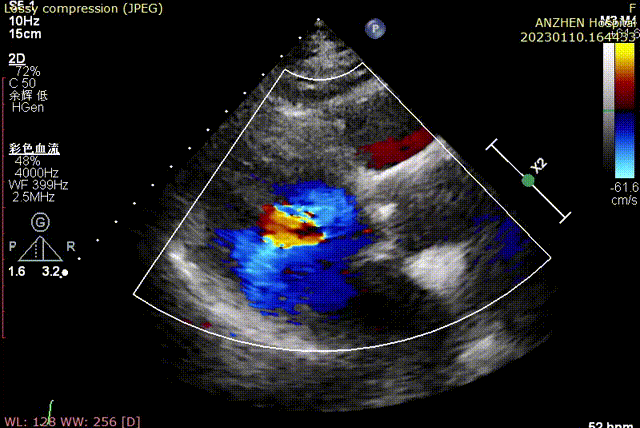

术前超声

术后超声

经DSA造影和超声等综合评估显示瓣膜释放位置完美,瓣膜工作稳定,术后即刻主动脉瓣上峰值流速:202cm/s、峰值压力阶差:15mmHg,平均压差:7mmHg,人工主动脉瓣瓣环内无反流,微量瓣周漏,患者临床症状和血流动力学明显改善。